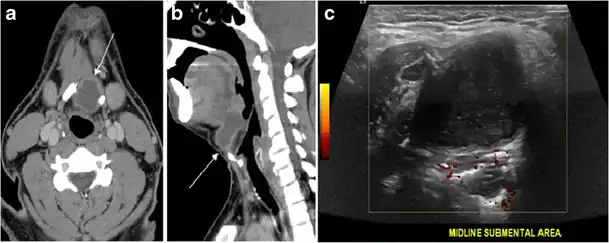

Fig. 13. A 27-year-old female patient known to have goiter. a, b Axial and sagittal enhanced CT scan images of the neck demonstrate a heterogeneously enhancing, enlarged thyroid gland with scattered calcifications (white arrow), cystic changes, and substantial retro-sternal extension (black asterisks). No lymphadenopathy or substantial airway narrowing.[1] -

Malignancy can coexist within the goiter and a CT scan may give a clue if there are abnormal cervical lymph nodes and/or signs of invasion. Retrosternal extension (Fig. 15) could affect the surgical approach, as a lower extent may require a partial or total sternotomy to facilitate complete resection. Therefore, the distance of the retrosternal extent from the sternal notch should be measured on a sagittal image.[1]